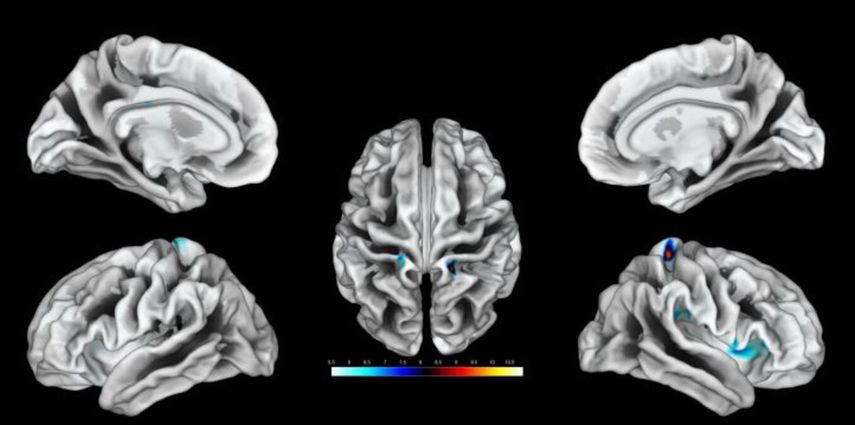

La conclusión es que tanto para mujeres como para hombres, la representación de los genitales en el mapa cerebral está cerca de la representación de la cadera.

No obstante, la ubicación precisa varía para cada mujer dentro de este área.

Después, para cada una de ellas, los investigadores determinaron los diez puntos más activados en el cerebro durante la estimulación y midieron el área obtenida.

"Hemos encontrado un vínculo entre el grosor de la zona genital y la frecuencia de las relaciones sexuales", especialmente en los últimos 12 meses, explica Heim.

"Cuanto más relaciones sexuales, más amplia es la zona".